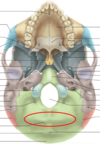

Reconozca la marca ósea encerrada en el círculo

Foramen magnum